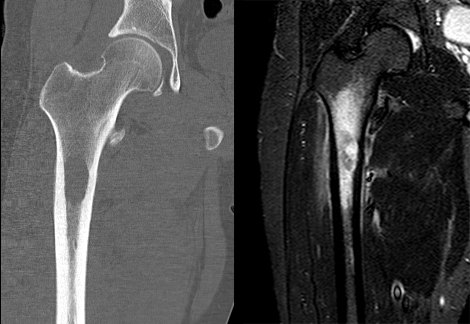

肿瘤对软骨的破坏

肿瘤对骨骺板和关节软骨的破坏是对骨破坏的继续。缺乏血管的骨骺板对恶性肿瘤有抵抗作用,骨骺板可暂时阻止肿瘤的蔓延,但当肿瘤进一步发展时, 骨骺板亦可被破坏,X 线平片或 CT 可表现为先期钙化带密度减低、中断或消失。MRI 可显示肿瘤从干骺端跨越骨骺板侵犯骨骺(图 15、图 16)。肿瘤突破关节软骨向关节腔发展时, 可表现为关节面破坏、塌陷(图 17), 关节腔内出现软组织肿块。少数良性骨肿瘤如软骨母细胞瘤, 亦可超越骺板向两侧发展或突入关节腔内, 此为肿瘤膨胀生长所致, 而非浸润性破坏。

图 15.骨骺板破坏:骨肉瘤

图 16.骨骺板破坏:骨肉瘤